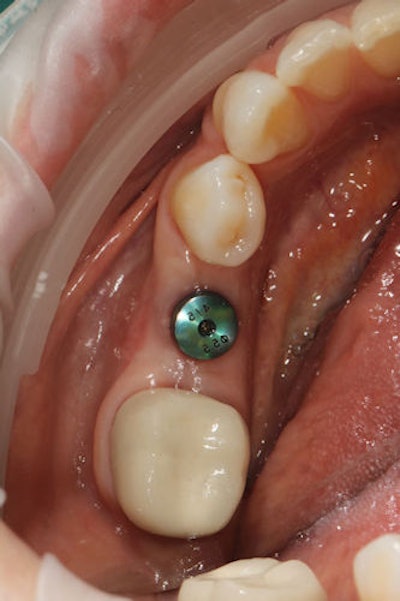

Clinically, the case proceeded with an intraoral view of the healing abutment (Figure 2). After removal, a ScanPost was placed and scanned using CEREC Primescan (Figure 3), capturing a full-arch digital impression with precise scan body positioning and soft-tissue contours.

Figure 2: The healing abutment in place.